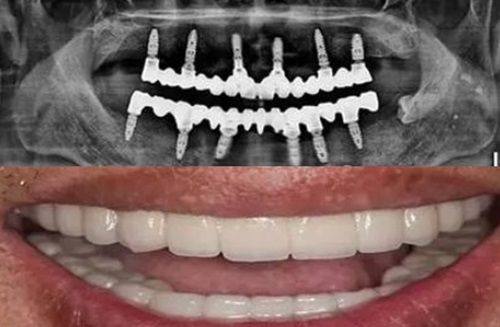

而对于需要进行深层洁治的患者,比如存在龈下牙结石、牙周炎症状的患者,则需要更高频率的超声波振动。这时候就需要像法国赛特力P5这类专精的深层洁治设备,其要求的频率达到28kHz以上,也就是2.8万赫兹以上。这类高频振动能够产生更强的穿透力,顺利进入牙周袋内部,震碎附着在牙根表面的龈下牙结石,同时有效清除牙周袋内的菌斑与炎性组织,帮助控制牙周炎症的发展。

第一个需要考虑的因素是牙结石的位置与硬度。龈上的牙结石通常硬度适中,附着在牙齿表面,使用2万至3.5万赫兹的频率就可以轻松震碎;而龈下的牙结石附着在牙根表面,位置更深,硬度也可能更高,这时候就需要使用28kHz以上的频率,比如赛特力P5这类设备,才能有效清洁。

综上所述,超声波洗牙的频率是影响清洁成效与口腔安心的核心因素之一。目前主流的医用超声洁牙机的振动频率普遍在2万至4.5万赫兹之间,这是经过临床验证的安心有效范围,能够满足绝大多数日常口腔清洁的需求。而像法国赛特力P5这类专精深层洁治设备,则需要达到28kHz以上的超声波频率,才能深入牙周袋内部,有效清除龈下的牙结石与菌斑,控制牙周炎症的发展。